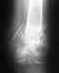

Здравствуйте! Ровно неделю назад мне был проведен остеосинтез обеих костей предплечья пластиной и штифтом. Дополнительной гипсовой иммобилизации после операции делать не стали, ношу руку в косынке. Беспокоит, что до сих пор есть выраженные боли в местах перелома костей при практически любых движениях рукой, при смене положения руки, при движениях запястьем. Боли кратковременного, простреливающего характера. Укладывание руки ночью превращается в целый мучительный ритуал. Кроме этого, имеет место слабая, но постоянная тянущая боль в руке, но она беспокоит меня меньше, думаю, это не до конца зажившая послеоперационная рана продолжает ныть. А вот острые боли в костях настораживают, беспокоюсь за надежность фиксации. В пятницу иду на снятие швов и меня выписывают из больницы. В связи с этим хочу узнать, стоит ли переживать из-за этих болей? нормальное ли это пока явление или не вполне? если нет, то что можно предпринять? контрольный рентгеновский снимок? или не делать ничего, пить обезболивающее и ждать, что пройдет само? спасибо.

Вы не показываете даже рентгеновский снимок. Заочно ничего определенного сказать не получится - неизвестно, как сопоставлены отломки, насколько прочно фиксированы. Какая пластина, сколько каких винтов где расположены - не угадать. Раз уж все равно запланирован очный прием, то все вопросы уместно задать врачу, который и очно может оценить состояние, и снимки посмотреть.